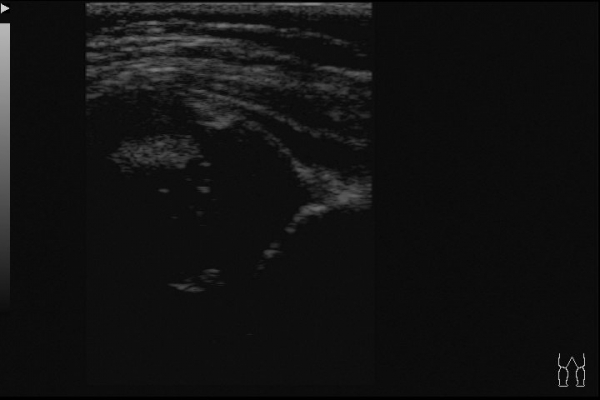

Вот еще пример, когда УЗИ картина не совсем соответствует истине:

Ребенок 6 месяцев, до обращения в наш центр неоднократно осмотрен ортопедами. Клинически -- полная норма, но насторожила какая-то чуть избыточная ротация в левом бедре. Решил выполнить УЗИ:

По УЗИ дисплазия слева, достаточно тяжелая. Может и подвывих, если придраться.

А на рентгене -- полный врожденный вывих, головка лежит вне сустава.

Тактика лечения -- другая, прогнозы - другие.